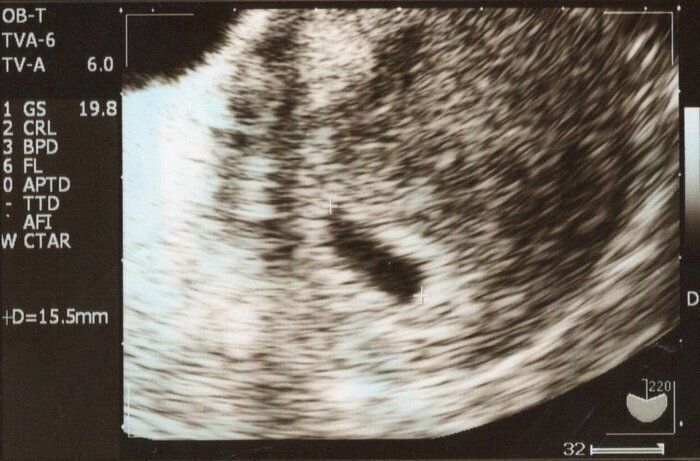

小吉さんの妊娠5週目のエコー写真

味覚の変化が気になって妊娠検査薬で調べたところ、陽性反応が出たため、翌日に早速、産婦人科へ行きました。これが最初に撮ったエコー写真です。中央左に見える黒い楕円が胎嚢ですが、妊娠に気づくのが早かったようで、この時点では「妊娠の兆候が見られる」とだけ言われ、確定は翌週に持ち越されました。